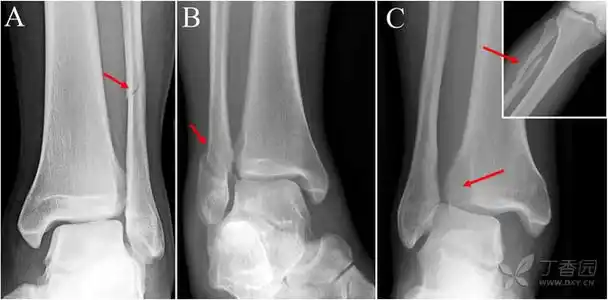

图4:胫腓联合损伤诊断测量线:a,胫腓骨重叠,b,胫腓骨间隙,c,内踝间隙.